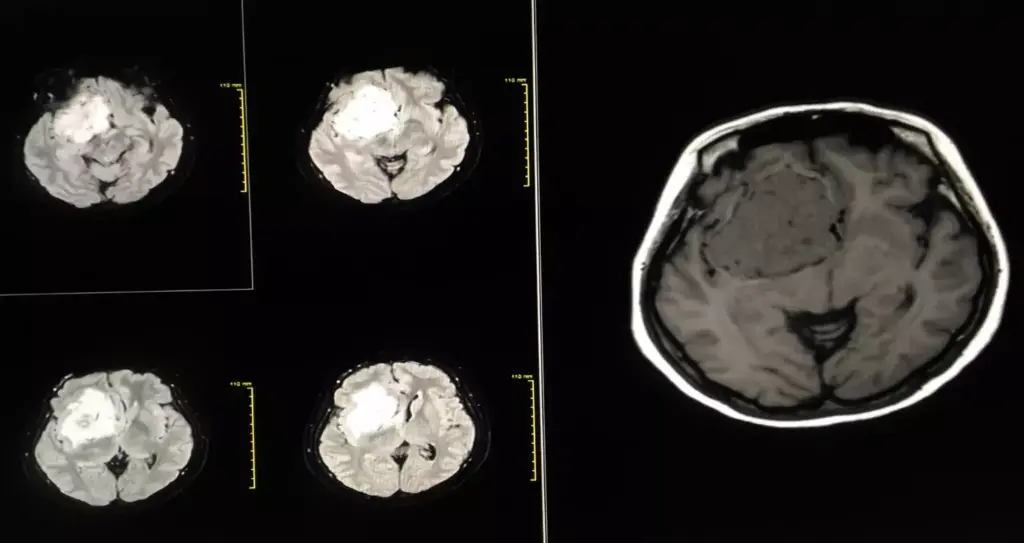

Brain Tumors